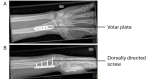

Spontaneous rupture of the extensor pollicis longus (EPL) tendon has been reported to be uncommon. Several possible causes and precipitating factors have been reported for this rupture, including prior surgery to the distal radius. We report the case of an 18-year-old male professional athlete who presented with an inability to extend their left thumb. They presented with this condition after open reduction and internal fixation (ORIF) for a fractured left distal radius. Findings were consistent with the rupture of the EPL tendon. The typical presentation of such a rupture is one to four months after ORIF surgery, a shorter delay than seen in the present case, which exceeds one year. They underwent surgical tendon transfer using the extensor indicis tendon, and a dorsally protruding surgical screw was removed from the volar aspect of the radius. In this case, we suggest that repetitive friction from the protruding surgical screw, following volar plating of a distal radius fracture, may have caused abrasion of the EPL tendon. This may have predisposed it to rupture. This can occur long after the placement of a volar plate and must be considered as a potential cause of an EPL tendon rupture.